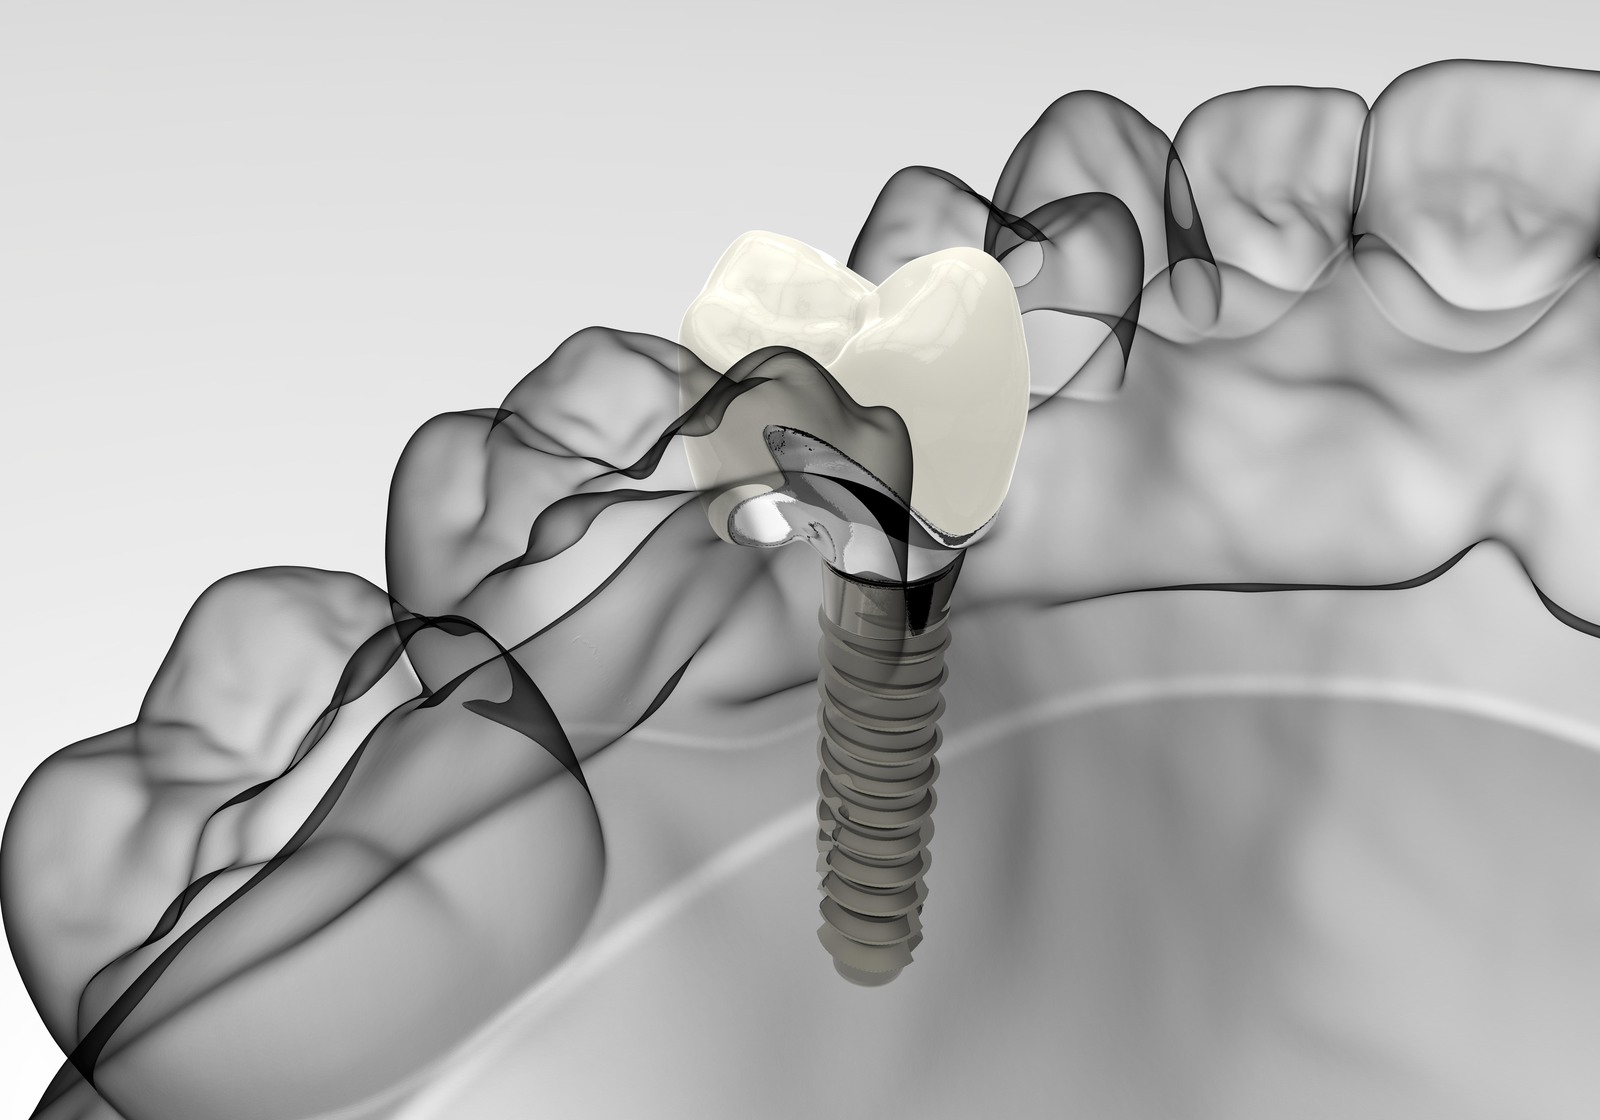

Research has found that a new nanocoating for dental implants inhibits bacterial growth and reduces the formation of bacterial biofilm on the implant surface.

Research has found that a new nanocoating for dental implants inhibits bacterial growth and reduces the formation of bacterial biofilm on the implant surface.

In the study, the research team, comprising scientists from the School of Biological Sciences, Peninsula Schools of Medicine and Dentistry and the School of Engineering at the University of Plymouth, created a new approach using a combination of silver, titanium oxide and hydroxyapatite nanocoatings.

The application of the combination to the surface of titanium alloy implants successfully inhibited bacterial growth and reduced the formation of bacterial biofilm on the surface of the implants by 97.5%.

Not only did the combination result in the effective eradication of infection, but it also created a surface with anti-biofilm properties that supported successful integration into surrounding bone and accelerated bone healing.

He commented: ‘Current strategies to render the surface of dental implants antibacterial with the aim to prevent infection and peri-implantitis development, include application of antimicrobial coatings loaded with antibiotics or chlorhexidine. However, such approaches are usually effective only in the short-term, and the use of chlorhexidine has also been reported to be toxic to human cells. The significance of our new study is that we have successfully applied a dual-layered silver-hydroxyapatite nanocoating to titanium alloy medical implants which helps to overcome these risks.’